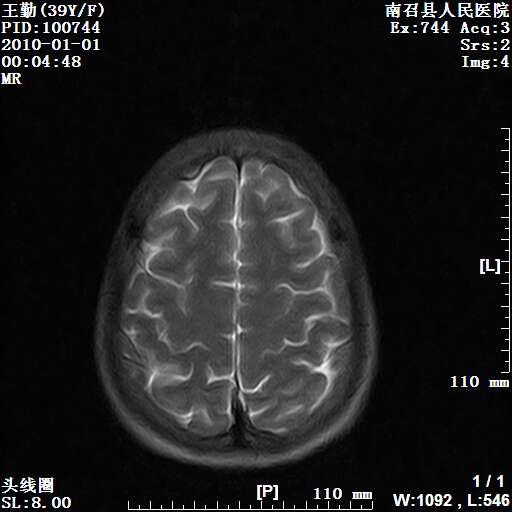

以下是引用随光逐影在2010-1-22 9:03:00的发言:[br]考虑左侧中颅窝(蝶骨翼区)脑膜瘤侵犯蝶骨翼并突入左侧眼眶。

以下是引用水过无痕在2010-1-22 14:55:00的发言:[br]一、定位:颅外占位;二、定性:恶性可能性大;三、组织来源:来源于左侧眼外直肌或其他部位;考虑为:横纹肌肉瘤>转移瘤>脑膜瘤.